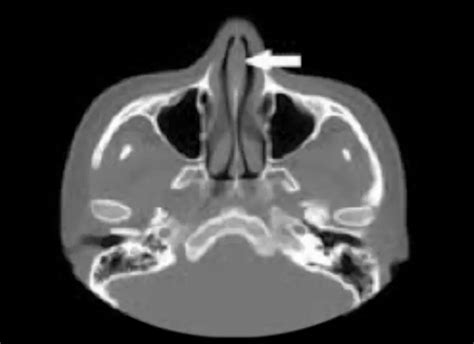

- Radiografías o tomografías de la cavidad nasal para visualizar cuerpos extraños, pólipos o tumores.

- Endoscopia nasal (rinoscopia) para una visualización directa de las fosas nasales y la posible extracción de cuerpos extraños o toma de biopsias.

Pólipos y Tumores Nasales

Si observamos cualquier bulto en la nariz, debemos consultar con nuestro veterinario, pues podría tratarse de un pólipo o tumor nasal. Estas afecciones pueden causar hemorragias nasales, además de obstruir, en mayor o menor medida, el paso del aire.

Los tumores en la cavidad y senos nasales son más frecuentes en perros mayores. Además de hemorragia y ruidos debidos al taponamiento, podemos observar secreción nasal y estornudos. El tratamiento de elección suele ser la cirugía. Los pólipos, que no son cáncer, pueden presentar recurrencia.